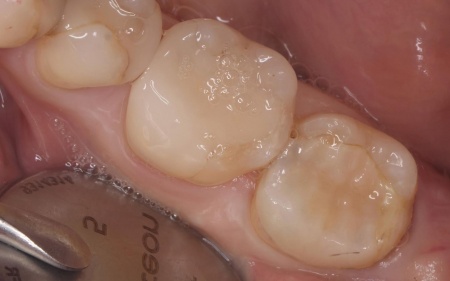

治療前